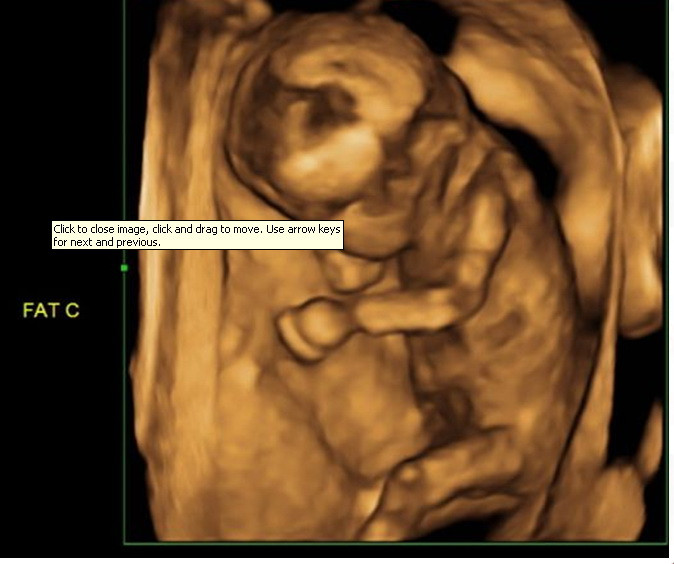

Vedeta ACASA Nicoleta Luciu este extrem de fericita. In urma ecografiei pe care telespectatorii au putut-o vedea astazi in premiera si exclusivitate la “Povestiri adevarate”, medicul specialist i-a dezvaluit sexul tripletilor.

Nicoleta Luciu si iubitul ei Zsolt Csergo au intrat in cabinet nerabdatori si foarte emotionati, iar rezultatul ecografiei le-a adus zambetul pe buze. “Suntem amandoi foarte entuziasmati si fericiti ca o sa avem doi baieti si o minune de fetita in familie. Eram foarte curiosi sa aflam sexul micutilor si ma bucur ca am putut sa-i vedem cum se misca in burtica. Unul dintre ei parea ca ne saluta, celalalt dadea din picioruse, iar fetita statea cu manuta pe langa cap, asemenea unei dive, de parca se ferea de reflectoare”, povesteste Nicoleta Luciu.